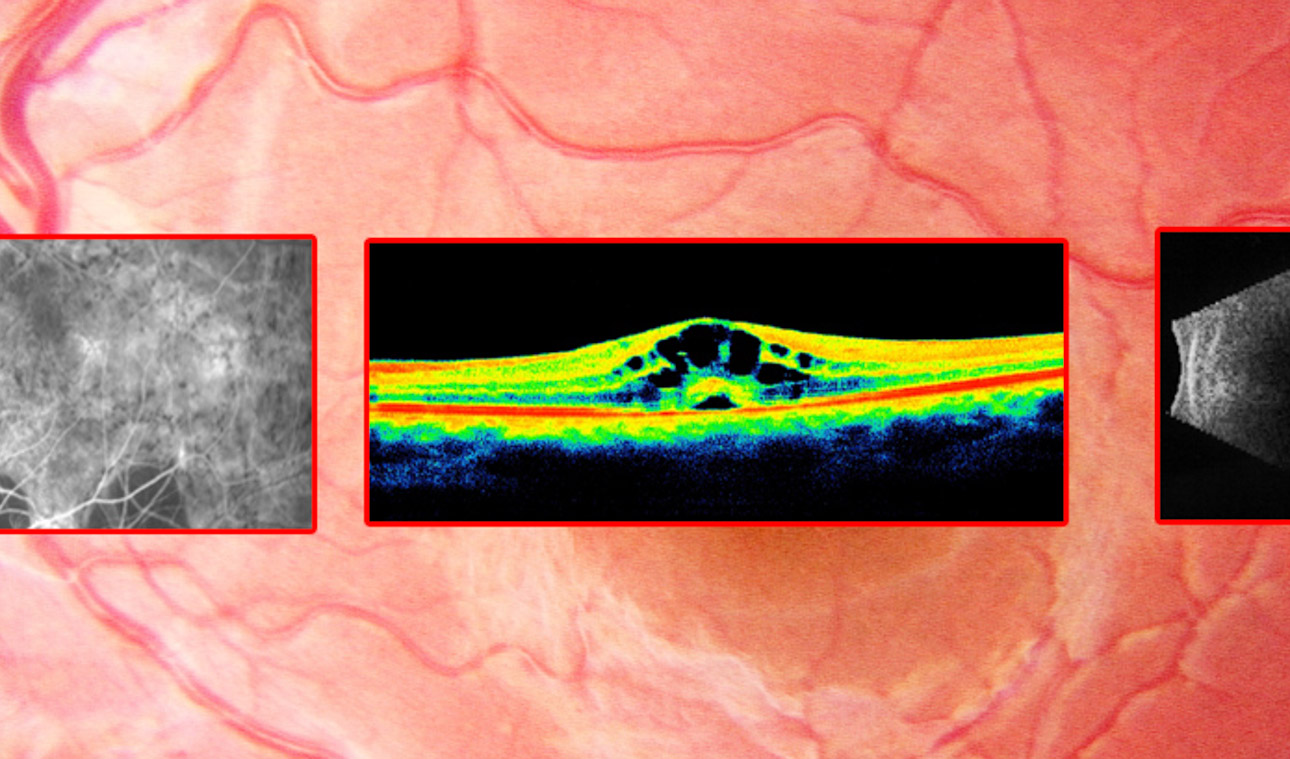

Fotolabor

Zur Poliklinik gehört u.a. der Bereich Makulafunktionsdiagnostik. Hier werden spezielle Untersuchungen mittels bildgebender Verfahren durchgeführt...